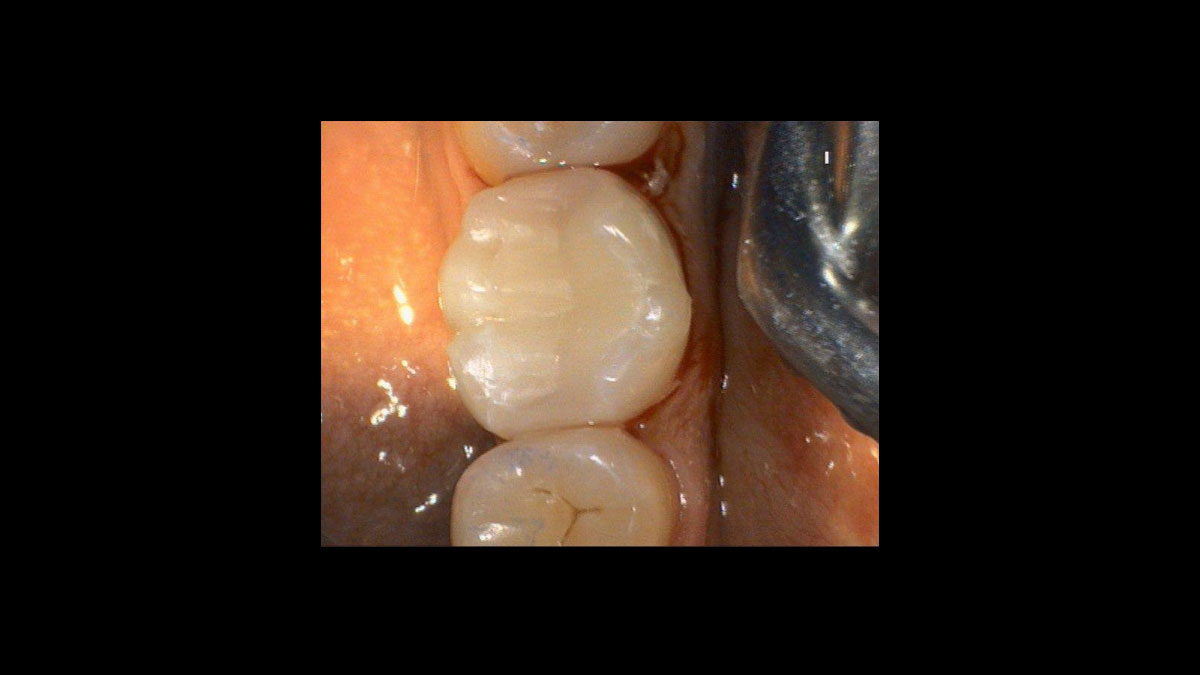

From www.aegisdentalnetwork.com

Periodontal Applications of the Diode Laser February 2010 Inside Diode Laser Treatment Effects The aim of this study was to investigate and compare the clinical, microbial, and inflammatory effects of a. Diode laser technology is well established for. conclusions and practical implications: The adjunct use of a 1064 wavelength diode laser with definitive srp. the clinical effect of diode laser in the treatment of the periodontal pockets in comparison with the. Diode Laser Treatment Effects.